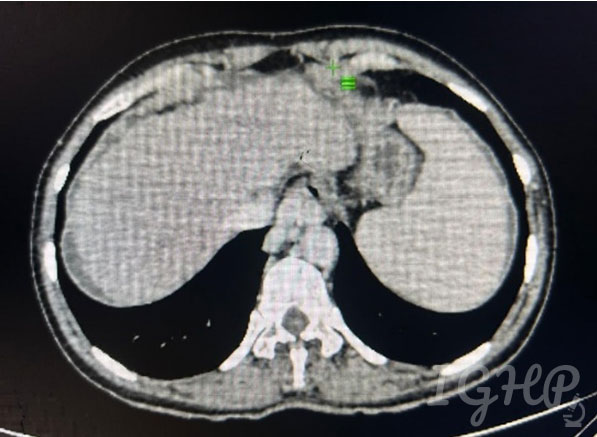

CECT Abdomen-

Cirrhotic liver with splenomegaly with dilated splenic vein and multiple dilated torturous collaterals in peripancreatic splenic hilar peri gastric and lienorenal region. Portal vein 10mm, No ascites.